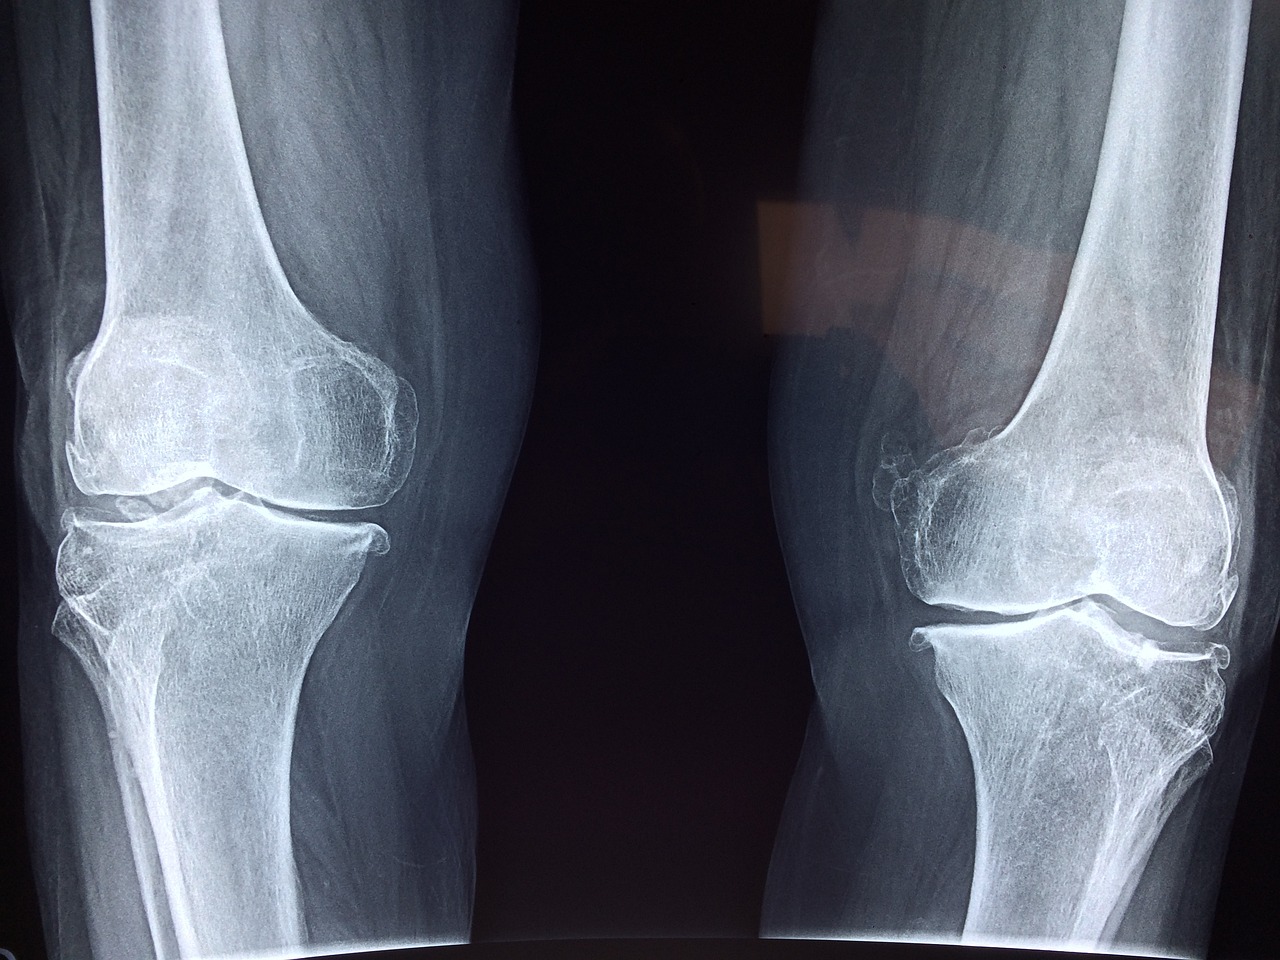

의사들의 말에 따르면 고관절은 신체에서 가장 중요한 관절 중 하나입니다. 우리의 체중을 하루 종일 지탱하고 움직임을 돕는 역할을 하기 떄문입니다. 하지만 나이가 들면서 자연적으로 연골이 닳는 현상이 벌어지고 근육이 약해지면서 통증이나 부상 위험이 커집니다. 특히 퇴행성 관절염과 골다공증은 중장년층에게 흔히 발생하는 문제이며, 고관절 골절은 심각한 문제를 일으킬 수 있습니다.